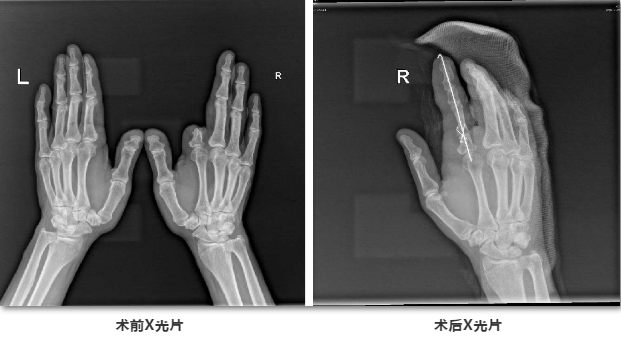

手指再造术前设计

经过多方打听和寻医,最终,曹先生选择了顺德和平外科医院进行右手示指再造,手中心雷彦文、吴祥主任医疗团队为其诊疗,最终决定将采用左足第二趾联合左足踇甲瓣移植再造右示指术。

断指再造

吴祥主任介绍,“右手示指Ⅳ度缺损”,面对这样一名功能和外观要求度高的患者,为了尽量保持示指的长度、功能、外观,采取了“建房子”的手术方法,简单来说就是“缺什么补什么”,例如:缺骨头缺关节,就补骨头补关节;缺皮肤缺指甲,就补皮肤补指甲。通过在身体其他部位取材,把”房子”内部填充完整。对比传统的足趾搬家再造,“建房子”理念的再造难度提高了很多。

他进一步解释,第二脚趾骨关节的功能是恢复手指的关节活动度;而大脚趾踇甲皮瓣的功能是尽可能让手指达到正常示指的外观。

吴祥表示,手术的难度在于,从脚上取下来的趾头要和右手示指的血管相吻合,要在放大二十倍的显微镜下用比头发丝还细的线,把血管吻合缝好并保证畅通。“手术有一定的风险,如果当时脚趾接到示指上不通血,那就麻烦了。”吴祥说,和平医院有扎实的显微外科基础,对于血管神经肌腱等接活有相当多成功的病例。

据了解,手术全程在高倍显微镜下,先精准选取部分足趾骨骼(或髂骨骨骼)与踇甲瓣,取材后对其进行精确修整,保证移植后与正常手指无差异,然后将血管、神经、肌腱和骨骼及皮肤方面进行再接修复,成功移植到受伤的手指部位。避免不必要的创伤。